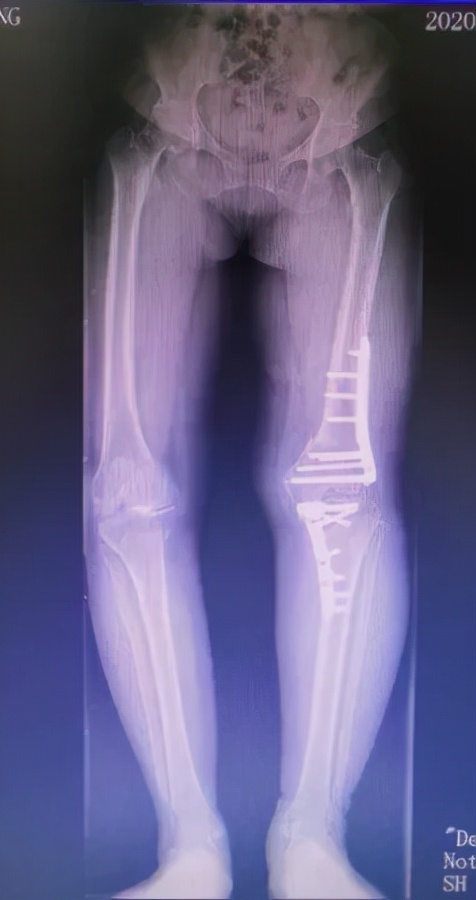

术后半年

通过术前在计算机上精确规划截骨线及矫正角度后,刘万军主任团队对赵女士的左膝同时进行了股骨远端截骨术+胫骨高位截骨术。先取左膝关节的正中切口,行内松解后,按标准手术行髌骨修整。股骨切骨完整后,试装假体复位,调试后用骨水密固定安装假体。之后取左膝关节屈膝90度,采用外侧倒T行切口,分离胫骨外侧组织,在胫骨平台远侧2cm处截骨,用C形臂X线机检查位置,反复检查下肢对线,在腓骨前方行内固定。手术进行的非常顺利,出血少,历时约3小时10分钟。术后赵女士的膝关节疼痛消失,膝内翻畸形得到明显改善。